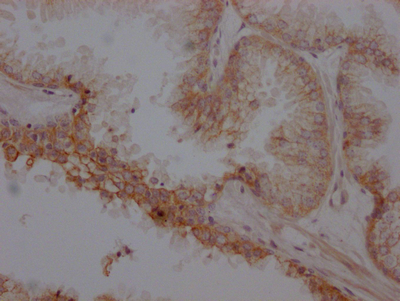

IHC image of CSB-RA286054A0HU diluted at 1:100 and staining in paraffin-embedded human endometrial cancer performed on a Leica BondTM system. After dewaxing and hydration, antigen retrieval was mediated by high pressure in a citrate buffer (pH 6.0). Section was blocked with 10% normal goat serum 30min at RT. Then primary antibody (1% BSA) was incubated at 4℃ overnight. The primary is detected by a Goat anti-rabbit IgG polymer labeled by HRP and visualized using 0.05% DAB.

CSB-RA286054A0HU